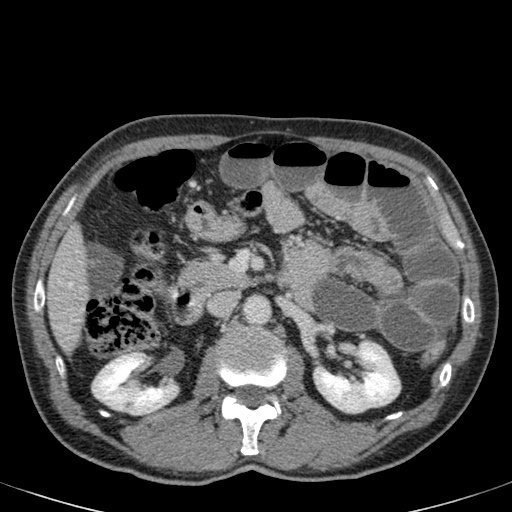

Đây là một bệnh nhân bị tắc ruột non.

Cuộn qua các hình ảnh.

Bạn có thể tìm thấy quai kín và nguyên nhân gây ra nó không?

Khi tiếp nhận bệnh nhân tại phòng cấp cứu với biểu hiện nghi ngờ tắc ruột non (SBO), điều quan trọng nhất chúng ta cần làm, ngoài việc chẩn đoán xác định, là xác định sự hiện diện hay vắng mặt của tình trạng thắt nghẹt.

CT là phương pháp chẩn đoán hình ảnh được lựa chọn trong đánh giá bệnh nhân nghi ngờ tắc ruột non.

Hình ảnh CT của tắc ruột non dạng quai kín phụ thuộc vào hai yếu tố:

- chiều dài đoạn ruột tạo thành quai kín

- hướng của quai ruột so với mặt phẳng tạo ảnh

Nếu quai kín ngắn và nằm trong mặt phẳng tạo ảnh, chúng ta sẽ thấy quai ruột hình chữ U hoặc chữ C.

Một hình ảnh quan trọng khác của tắc ruột dạng quai kín là các quai ruột non giãn xếp theo hình nan hoa với các mạch máu mạc treo hội tụ về một điểm trung tâm.

Hình ảnh này hầu như luôn do xoắn ruột non gây ra.